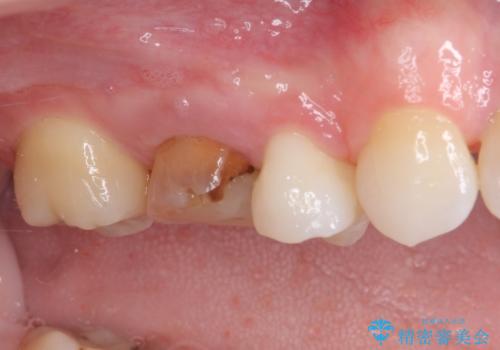

- 虫歯により神経を取り除いた前歯の変色が気になるとのことで来院された患者様です。

レントゲン写真より、歯根の炎症が認められなかったため、ファイバーコアによる土台築製後、オーダーメイドタイプのオールセラミッククラウンにて補綴することとしました。